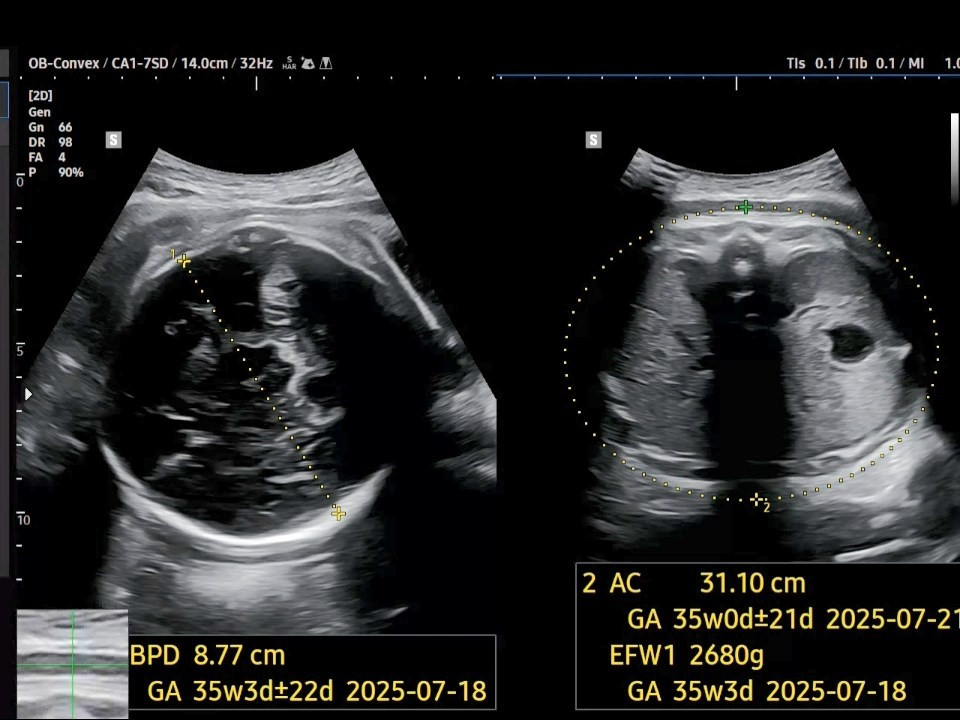

2. 태아 머리직경(BPD: Biparietal Diameter)은 8.77㎝이고, 태아 복부 둘레(AC: Abdominal Circumference)는 31.10㎝이네요. 둘 다 아주 조금 증가한 수치입니다. 임신 주수보다 약 2주 정도가 작은 상황이네요.

38주 BPD.jpg [38주 차 머리직경과 복부 둘레]